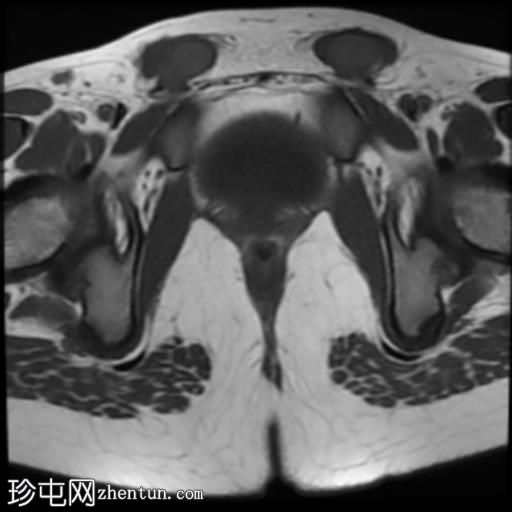

轴位

T2加权像

脂肪抑制序列显示:

女性外生殖器

子宫、宫颈、阴道上2/3及卵巢缺失

双侧睾丸异位,沿腹股沟管清晰可见

MRI表现符合伴女性外生殖器的雄激素不敏感综合征(男性假两性畸形)。